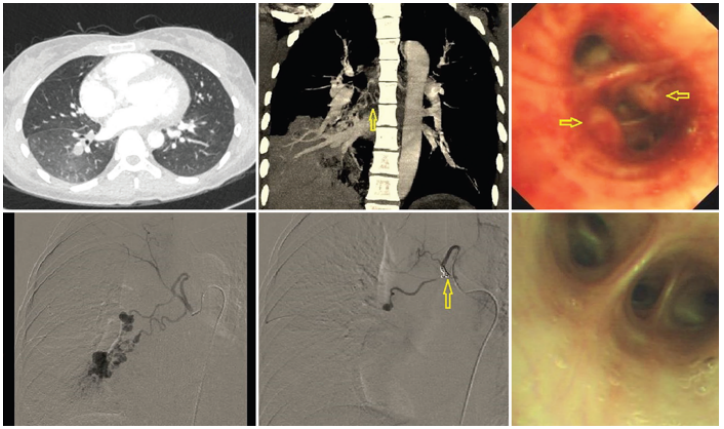

CT血管成像(CTA)表现:病变的支气管动脉主干增宽,明显迂曲,管腔没有逐渐变细的趋势,符合“恒径动脉”的表现。气管镜表现:光滑性结节样隆起;充血粗糙,凸起表面覆盖黄白色分泌物形成“小白帽”样表现。支气管动脉造影:病变部位血供丰富,支气管动脉迂曲扩张呈串珠状(图8-图10)

图片

图8  支气管动脉迂曲扩张,呈串珠状

图9  支气管动脉走行于黏膜下,形成结节样隆起

图10  Dieulafoy'病